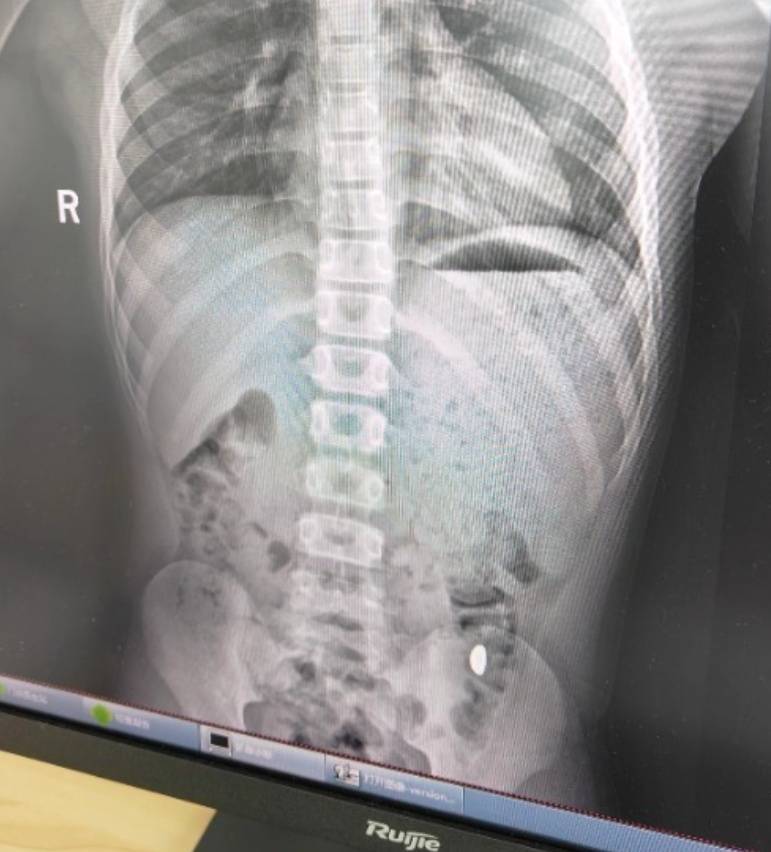

纪女士说,她起初以为儿子在开玩笑,当确认儿子真的吞了金豆子时,她也是哭笑不得币圈神话。“我每天都提醒他不能在外面拉屎,这个屎有点贵。”纪女士说,她等了5天,对着大便扒拉了两次还是没有找到金子,于是10月26日,她就带儿子去了医院。“上午去的医院下午就拉出来了。”纪女士说。

右下加亮点为金豆币圈神话。